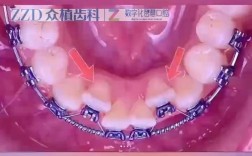

不拔牙矫正牙齿是通过非拔牙方式解决牙齿排列和咬合问题,主要适用于牙齿轻度至中度拥挤、牙弓空间不足但可通过扩弓、磨牙移动或邻面去釉等方式获得间隙的患者,整个过程需严格评估口腔状况,通过精准方案设计逐步调整牙齿位置,最终实现功能与美观的平衡,术...

可以不拔牙矫正牙齿吗?这是许多正畸患者最关心的问题之一,随着正畸技术的进步和理念的更新,越来越多的牙齿问题可以通过不拔牙的方式得到有效矫正,但“不拔牙”并非适用于所有情况,其可行性需要结合患者的牙齿拥挤程度、颌骨发育情况、咬合关系、面部美学...

磨牙前移是正畸治疗中常见的牙齿移动方式,主要用于解决后牙缺失、后牙反颌、深覆盖或关闭拔牙间隙等问题,其原理是通过施加持续、轻柔的生物力,引导磨牙向近中(靠近中线)移动,同时通过支抗控制确保其他牙齿不受影响,最终建立稳定的咬合关系和美观的牙列...